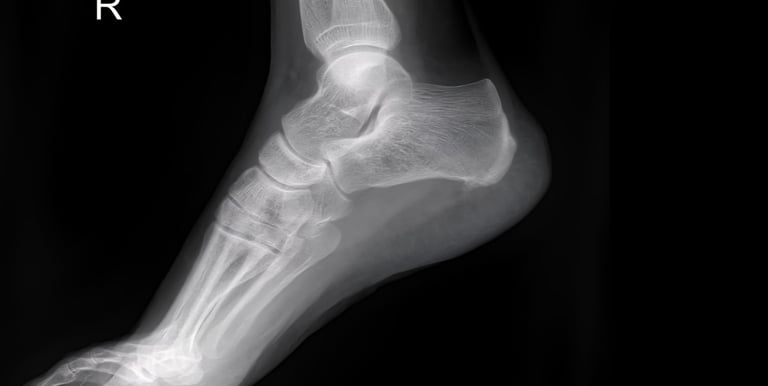

Foot & Ankle X-rays

Precise digital imaging for foot, ankle, and toe injuries, including fractures and joint alignment. We provide high-resolution views for orthopedic diagnostics and occupational health clearances.